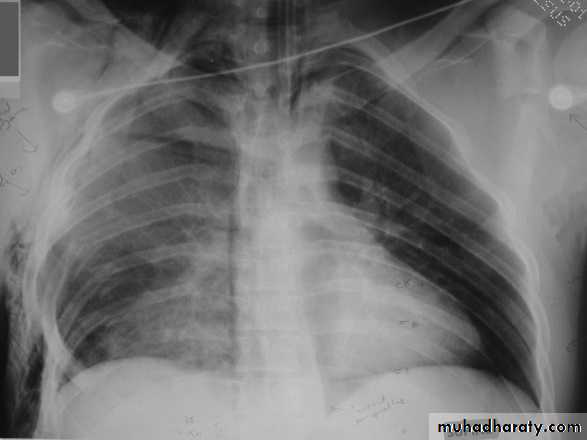

Hemothorax

X-ray hemothorax

X-ray pneumohemothorax